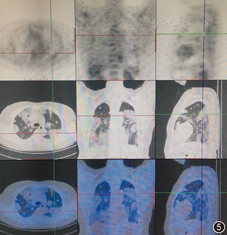

初步诊断为肺部多发结节原因待查。于我院门诊查血常规白细胞为5.15×109/L,中性粒细胞为0.52,嗜酸粒细胞百分比为0.09,C反应蛋白(CRP)为2 mg/L。1-3-β-D葡聚糖(G试验)、血清半乳甘露聚糖试验(GM试验)、隐球菌荚膜抗原阴性;抗核抗体(ANA)阳性(颗粒型1∶320,胞质型1∶320,均质型1∶320),抗ds-DNA(IIF法)阴性,抗dsDNA(ELISA法)为202 IU/ml(正常参考值:<100 IU/ml),抗中性粒细胞胞质抗体(ANCA)阴性。总IgE为73 kU/L(<100 kU/L)。肿瘤标志物细胞角蛋白19片段为5.7 μg/L(正常参考值:<3.3 μg/L),组织多肽抗原为150.1 U/L(正常参考值:<120 U/L),胃泌素释放前体为91.9 ng/L (正常参考值:<69.2 ng/L)。肺功能通气功能正常,支气管舒张试验阳性,FEV1改善率为12.6%(290 ml)。胸部高分辨率CT(HRCT)显示双肺多发大小不等、形态不规则团块实变灶(图2,图3,图4)。全身PET-CT显示双肺多发磨玻璃及软组织密度实变灶,葡萄糖代谢轻度增高(图5)。肛周葡萄糖代谢增高灶,考虑痔疮可能大。脑部、骨骼、肝脏等其余脏器未见葡萄糖代谢异常灶。